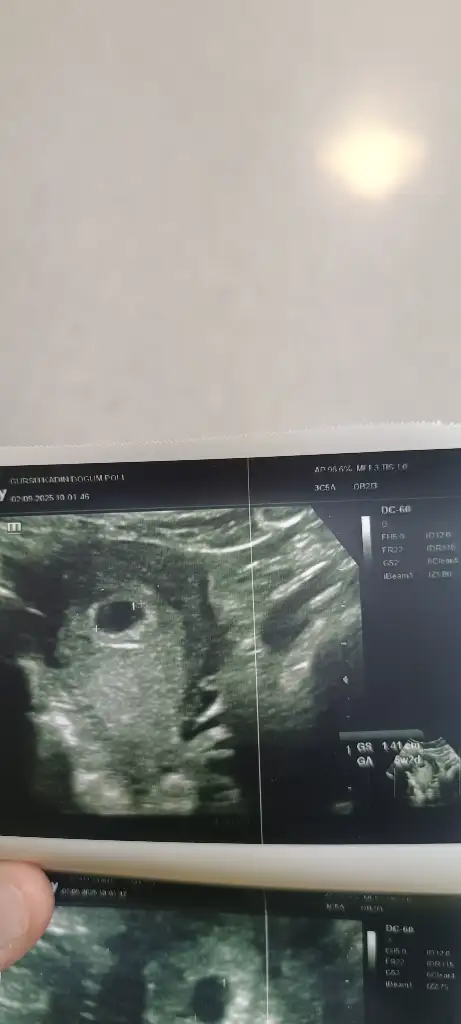

KızMerhaba kızlar 10+2 haftalık biliyorum daha çok erken ama keseden tahmin edenler olabiliyor rica etsem bakar mısınız erkek mi kız mı

Ben anlamıyorum ama kese şekline göre kız gibi çünkü düzgün yapıda sanırım yolk da sağ da olunca oda kız diye biliyorum tabi bunların hepsi bir teori sağlıkla gelsinArkadaşlar bana da yorum yapabilecek birisi var mı acaba

Çok sağol canım sağlıkla gelsin dediğin gibi ama insan merak ediyor işte iki oğlum var Rabbim sağlık versin bide kızım olsun çok isterimBen anlamıyorum ama kese şekline göre kız gibi çünkü düzgün yapıda sanırım yolk da sağ da olunca oda kız diye biliyorum tabi bunların hepsi bir teori sağlıkla gelsin